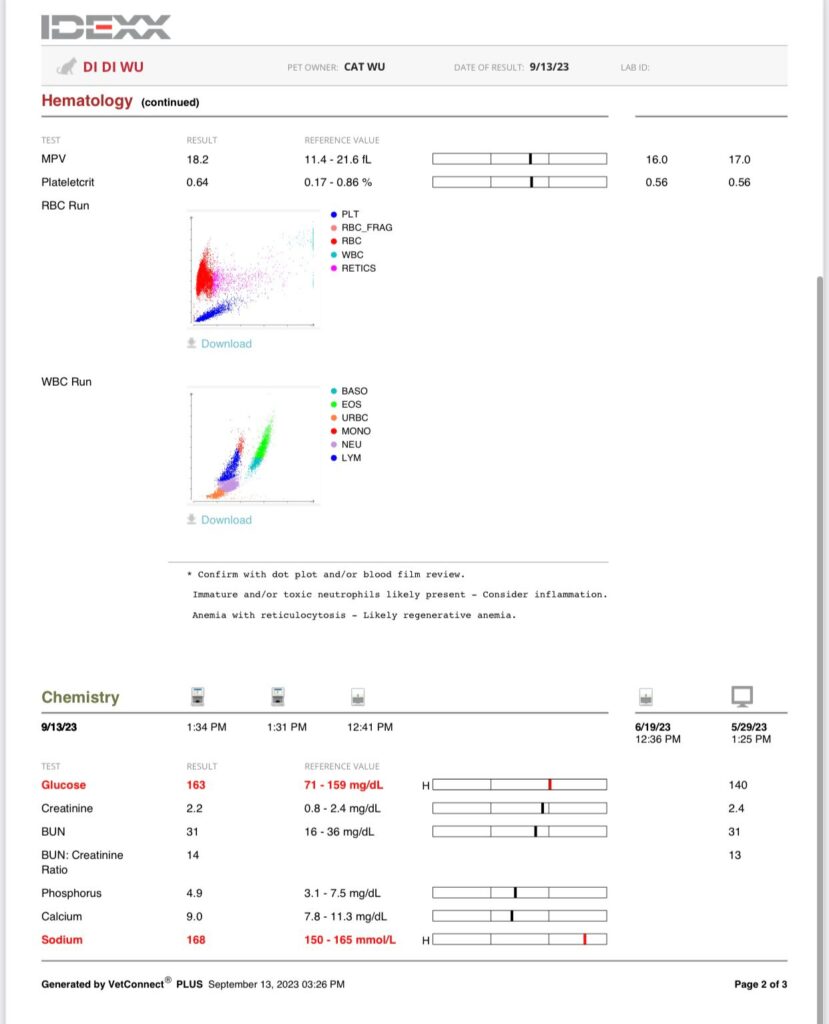

3.49kg – drop 180g in 4 days. V drastic weight change.

Got heart mur mur – taken probnp then

HR 240

Stomach so far ok.

Gum pale

To taken Cbc, Chem 15, lytes, probnp, pancreatitis.

Taken bp using from right leg.

His bp at resting is abnormality high. But can due to heart, kidney or ???

Results: probnp normal. So mur mur due to anemic?

anemic for sure. HCT 21% plus I’ll start him on darbepoetin for sure too. Now is he needs ab? Waiting for dr nally to send summary.

I was worried about didi extreme high retic: “Re Didi – internal bleeding less likely as BUN is still normal and no black poo noticed? More of something else infectious/inflammation going on – mouth/nose/UTI?/pancreatits/neoplasia. The CREA was high end normal it may be higher as he is very skinny”

New treatment plan for Didi

1. Ursofalk 15mg/kg -> stop – yeah but kns I just spent $100 on it arghhhhhhhhh

2. Subcut on off -> continue 80mls 1x daily, monitor RR closely

3. B12 b com -> continue

4. Sam e on off -> stop – why? Erm but of cos can stop he can’t stand oral med

5. Buprenophine on off -> continue 2x daily

6. Ornipural stop

7. Gabapentin on off -> not necessary if on bupre

*8. Start doxycycline and repeat CBC in 1week, kiv add-on marbo if no improvement* – ok so start ab. Erm didn’t mention darbepoetin? Erm maybe ok I’ll do Cbc in 1 week then decide to start darbo or not

*9. Repeat BP as well while on doxy and bupre, hypertension may be due to pain/anaemia*

*10. Start maropitant nasal drop* – have to try mix Tmr. Not sure got time or not